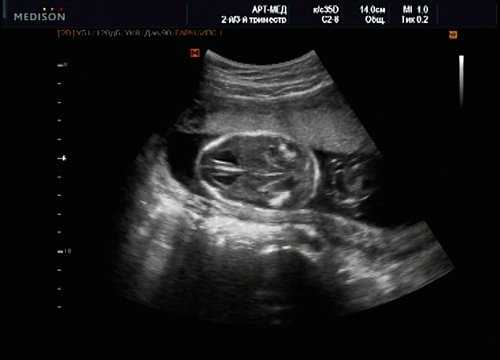

Беременная М., 21 года. Впервые обратилась в клинику в срок 20 нед беременности. Исследование проводилось на аппарате SonoAce-R7 (Samsung Medison) с использованием режима поверхностной объемной реконструкции 3D/4D. При изучении позвоночника плода в трех плоскостях костных деформаций не выявлено. В грудном отделе позвоночника обнаружено тонкостенное кистозное образование с анэхогенным содержимым, стебельчатой формы (рис. 10-12). Степень "прозрачности" содержимого была выше околоплодных вод, что позволяло идентифицировать его как ликвор. В проекции грыжевого выпячивания располагалась петля пуповины, дифференциальную диагностику которой без труда удалось провести с помощью ЦДК (рис. 13).

Рис. 10. Беременность 20 нед. Менингоцеле: типичное кистозное образование стебельчатой формы.

Рис. 11. Беременность 20 нед. Менингоцеле.

Рис. 12. Менингоцеле. В сагиттальном срезе видна неровность кожи в проекции расщелины.

Рис. 13. Петля пуповины в режиме ЦДК.